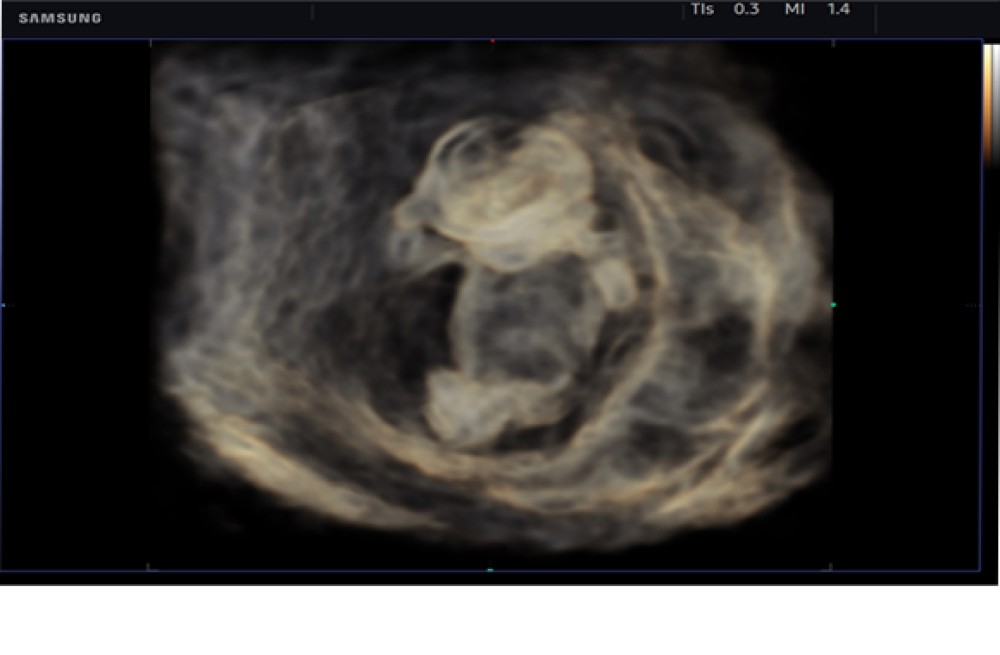

RealisticVue™: Yüksək dəqiqlikli 3D anatomiya təsvirini göstərir, detallar və real dərinlik qavrayışı ilə. İstifadəçi tərəfindən seçilə bilən işıq istiqaməti, daha yaxşı müəyyən edilmiş anatomik strukturlar üçün incə kölgələr yaradır.

Samsung HS40 çoxşaxəli, orta səviyyəli ultrasəs sistemidir və obstetrika, ginekologiya, muskuloskeletal (MSK), abdominal, pediatrik, kiçik orqanlar, urologiya və vaskulyar görüntüləmə daxil olmaqla geniş klinik tətbiqlər üçün yüksək keyfiyyətli təsvir təmin edir. O, diaqnostik etibarlılığı və iş prosesinin səmərəliliyini artırmaq üçün qabaqcıl təsvir texnologiyalarını istifadəçi dostu xüsusiyyətlərlə birləşdirir.